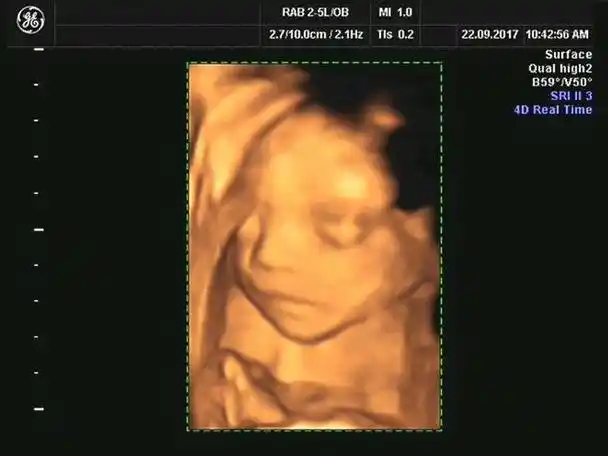

做四维看男孩女孩诀窍,如何通过四维照片上的